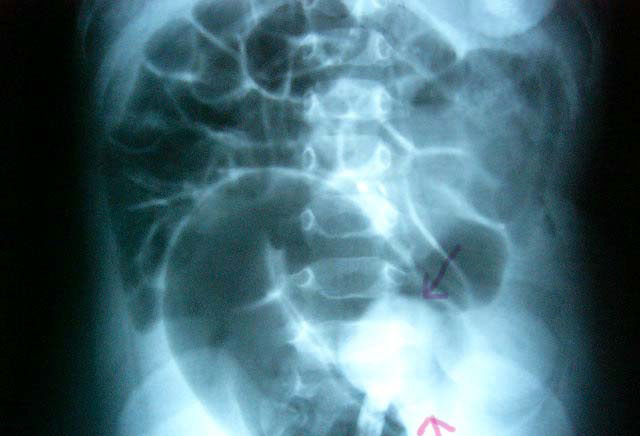

肠扭转的发生见于多种原因造成。解剖方面的因素是引起扭转的先决条件,而生理或病理方面的因素是其诱发因素。肠袢发生扭转的原因有三个重要的因素:

(一)肠袢和其系膜的长度比肠袢两端根部间的距离相对地过长,即容易发生扭转。

(二)在上述解剖因素的基础上,如肠袢本身的重量增加,由于重力的关系容易促使扭转发生,扭转后也不易自行复位。所以在临床肠扭转常见于饱餐、食物内纤维残渣多、大便秘结,肠腔内有蛔虫团、肠壁上有较大肿瘤、先天性巨结肠等情况下。

(三)外力推动,强烈的肠蠕动和体位的突然改变,如身体突然旋转用力弯腰,也能促使肠扭转的发生,因些,避免在饱餐后立即进行重体力劳动,尤其是需要身体前俯和旋转的劳动,对预防肠扭转有一定意义。